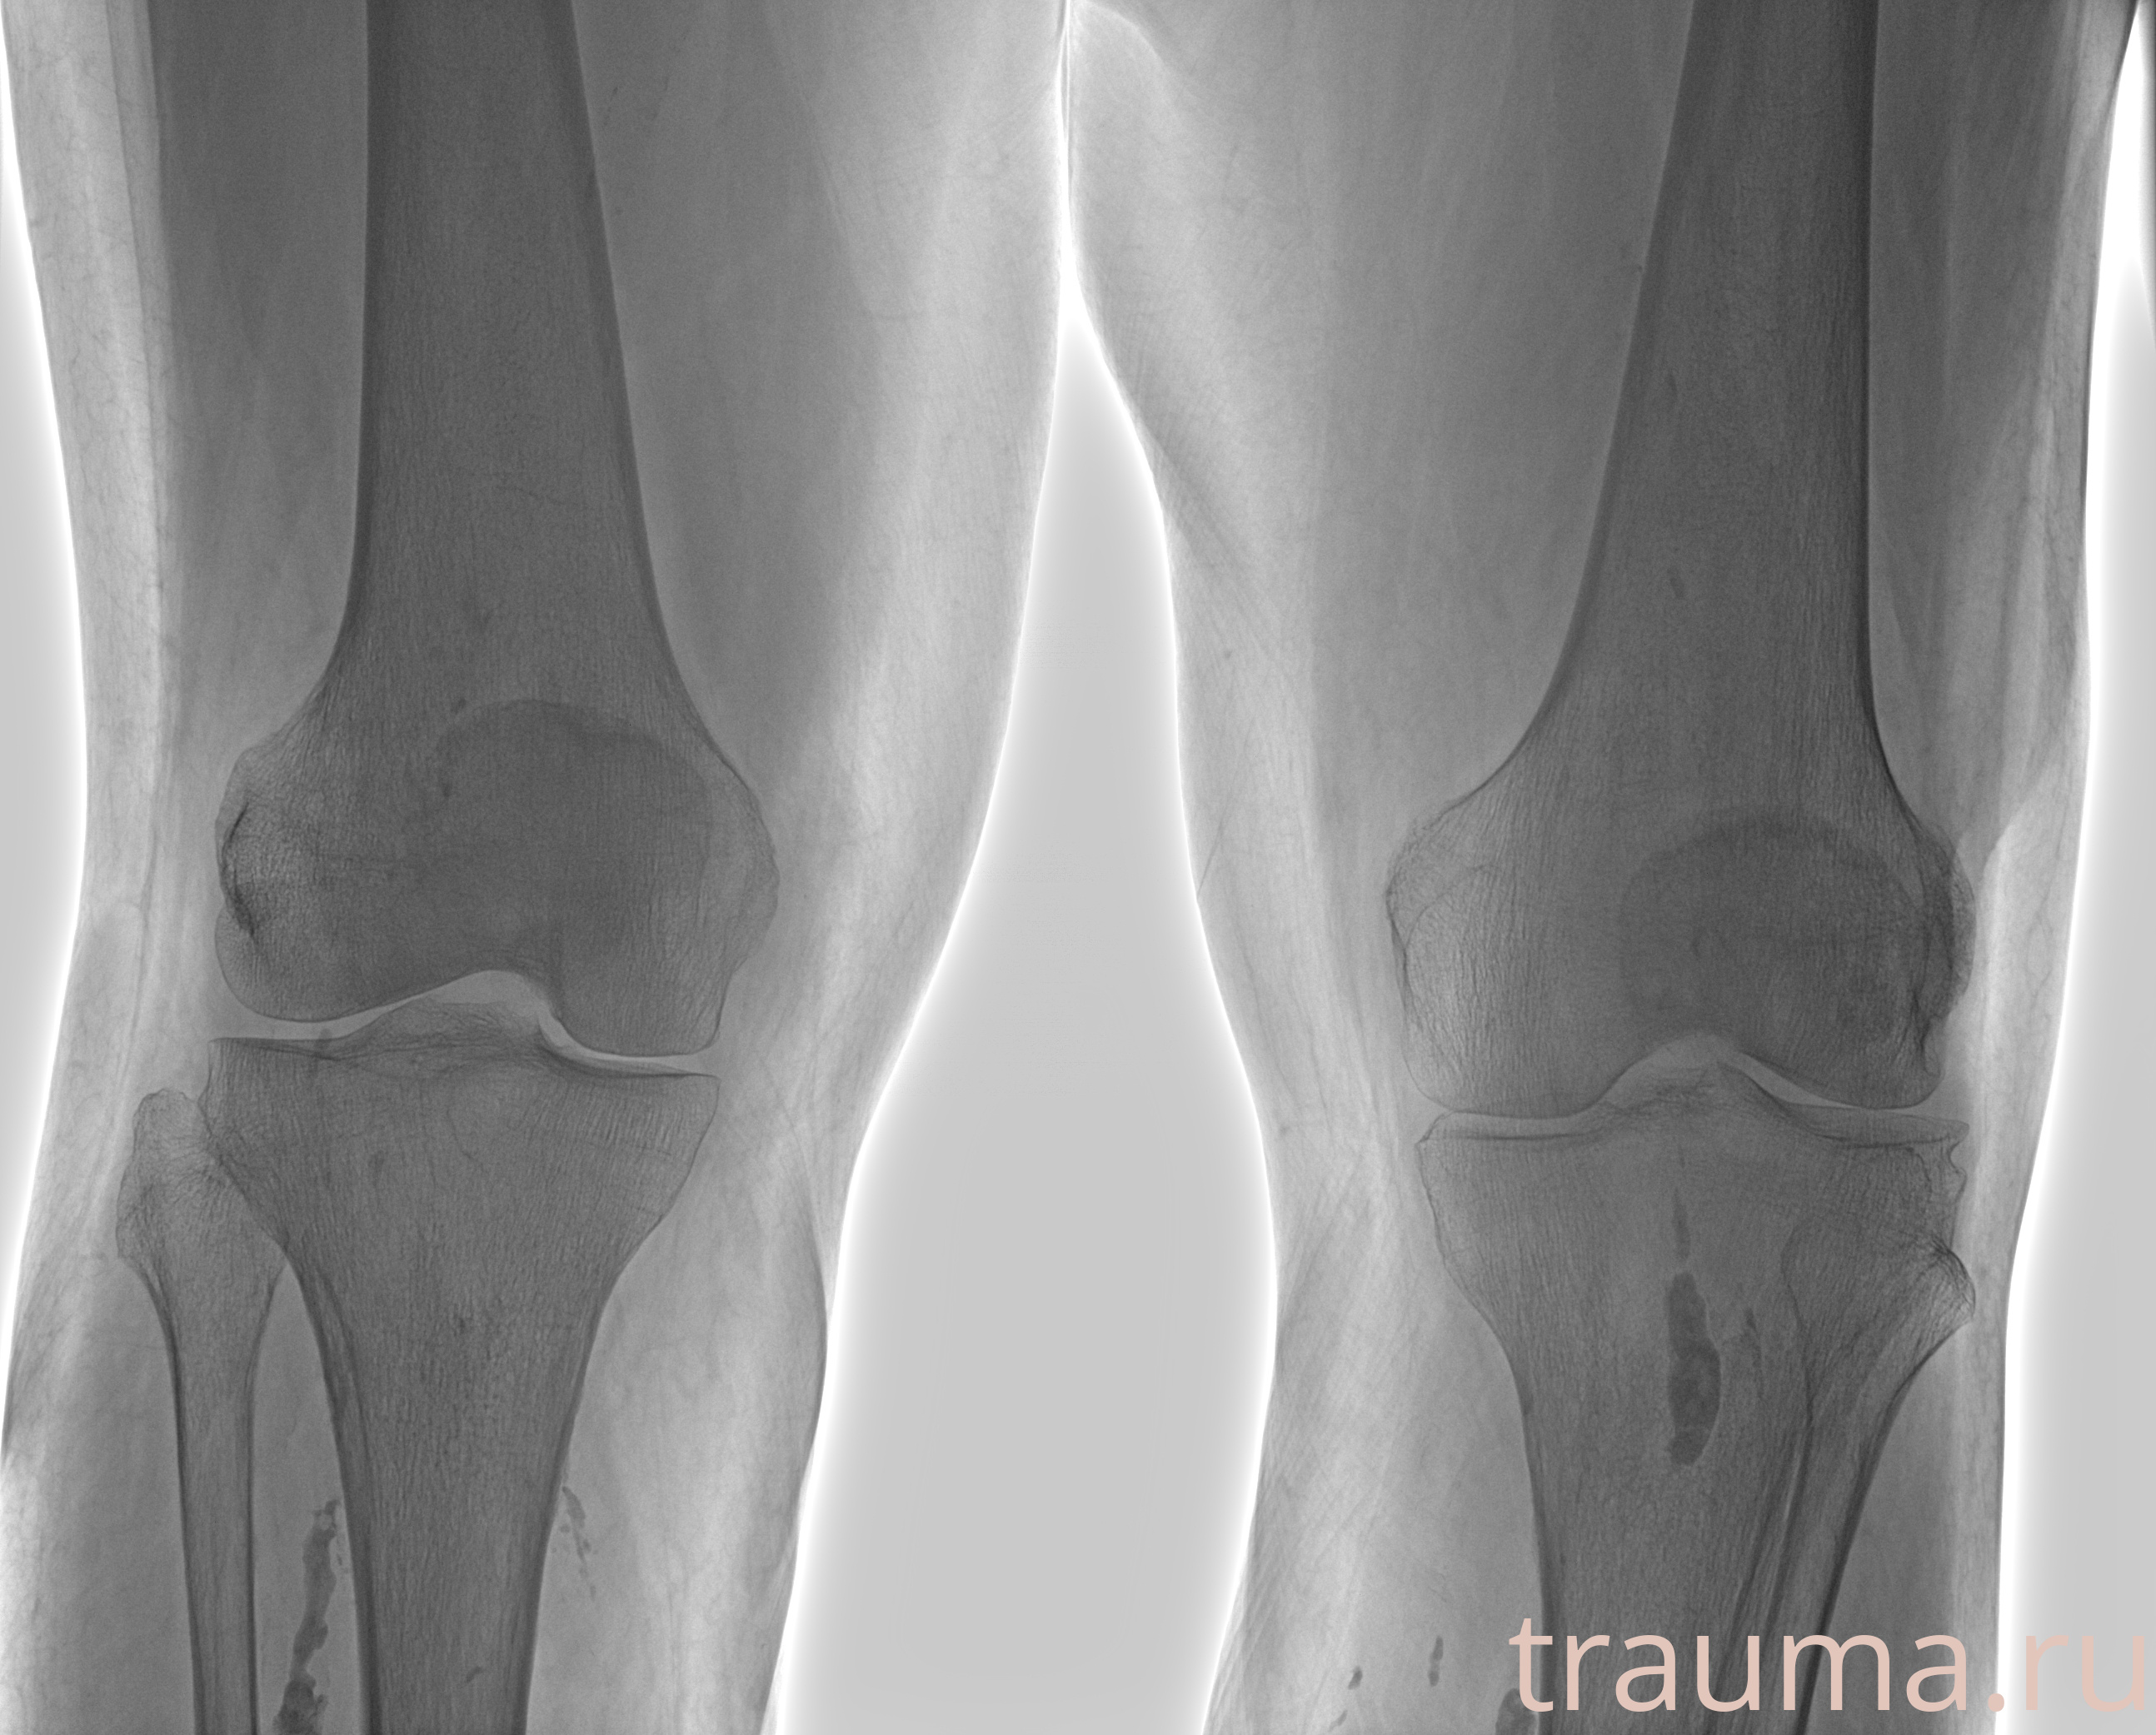

Рентген на дому: по вашему адресу приезжает врач-рентгенолог, травматолог-ортопед с мобильным рентгеновским аппаратом, проводит диагностику травмы или заболевания, делает необходимые рентгенограммы, дает рекомендации по дальнейшему лечению. Получить качественные снимки в домашних условиях возможно благодаря уникальной методике, разработанной МосРентген Центром для института  Склифосовского